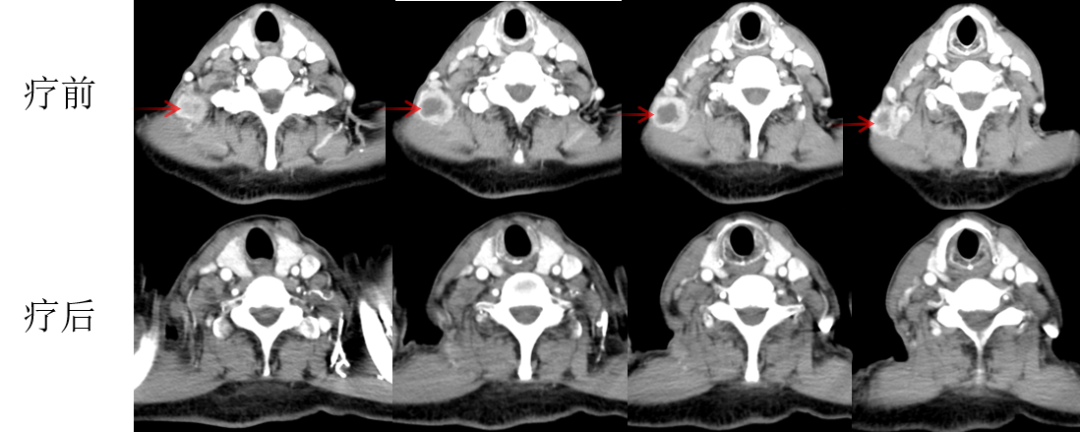

林老先生,67歲,患者2024年8月因咳嗽、咳痰,并發(fā)現(xiàn)頸部包塊入院。入院后經(jīng)CT檢查發(fā)現(xiàn),肺內(nèi)及頸部可見多發(fā)腫瘤病灶(見圖)。于2024年8月21日行超聲引導(dǎo)下頸部淋巴結(jié)穿刺活檢術(shù)。術(shù)后病理提示:右頸轉(zhuǎn)移性肺腺癌。頭部磁共振檢查顯示,顱內(nèi)多發(fā)腦轉(zhuǎn)移瘤病灶(見圖)。診斷為肺腺癌,腦、頸部淋巴結(jié)、肺內(nèi)多發(fā)轉(zhuǎn)移IVB期。進(jìn)一步對(duì)患者腫瘤組織進(jìn)行腫瘤組織基因檢測(cè)和免疫檢查點(diǎn)分子——細(xì)胞程序性死亡配體1(PDL1)檢測(cè)。

圖注:CT檢查,肺內(nèi)及頸部可見多發(fā)腫瘤病灶。

患者基因檢測(cè)結(jié)果為陰性,沒有找到具有靶向治療藥物的突變基因。此外,患者年齡較大,體質(zhì)非常瘦弱,全身多發(fā)轉(zhuǎn)移病灶,為治療帶來了巨大的挑戰(zhàn)。然而,患者PDL1檢測(cè)顯示,PDL1高表達(dá)(PD-L1患者TPS98% CPS100%),提示免疫治療有效率較高。潘振宇教授團(tuán)隊(duì)為患者制定了個(gè)體化精準(zhǔn)腫瘤治療方案,患者于2024年9月21日開始接受頭部放療。采用最新一代智慧化精準(zhǔn)放療系統(tǒng)——Halcyon“速銳刀”,成功控制患者全部顱內(nèi)病灶。治療過程順利,沒有副反應(yīng)發(fā)生。隨后,給予患者每3周1次免疫治療。經(jīng)過3次免疫治療后復(fù)查,患者肺內(nèi)病灶顯著縮退,癥狀明顯恢復(fù),沒有明顯副反應(yīng)發(fā)生。目前狀態(tài)恢復(fù)良好,生活完全自理。

圖注:治療后復(fù)查胸部CT顯示,肺內(nèi)病灶明顯縮小,頸部淋巴結(jié)轉(zhuǎn)移病灶基本消失。